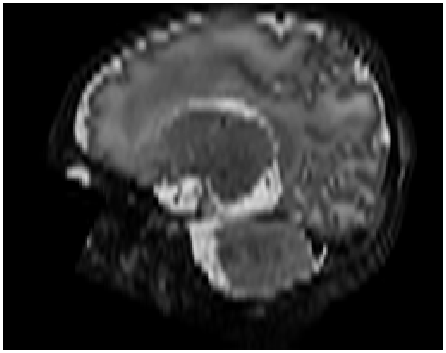

Figure 10: Qualitative comparison of image synthesis performance on neonatal brain MRI (dHCP dataset) between conventional interpolation methods and proposed approach. Original volumes with slice thickness and spacing of 0.5 mmtimes0.5millimeter0.5\text{\,}\mathrm{mm} were downsampled to 2.5 mmtimes2.5millimeter2.5\text{\,}\mathrm{mm} by applying a Gaussian blur before including every fifth slice in the test volume. Differences between reference (minuend) and synthesized slice (subtrahend). Blue corresponds to negative and red to positive differences. Image intensities are scaled to a [0,1]01[0,1] range. All difference images use the same color scale [1,1]11[-1,1].

Visual inspection of Figure 10 conveys that our proposed approach was able to synthesize excluded high-resolution axial slices more accurately than cubic B-spline interpolation. These results are corroborated by the coronal and sagittal views revealing that volumes generated by the proposed method are less blurry and contain smoother transitions between slices compared to volumes generated by the conventional interpolation method.